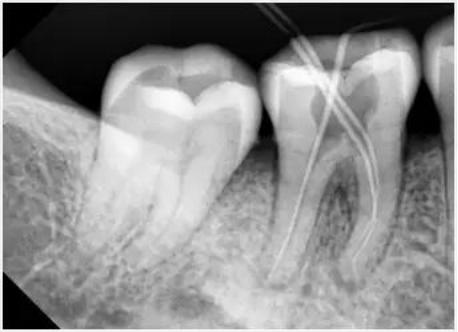

牙科医生们按照标准操作手法全面评估患者,在明确了患者的根管解剖形态、根管弯曲程度及直径等具体情况之后,为了获得标准的根管形态,即基本维持根管原有形态,不改变或过度扩大根尖孔的位置,使根管形成一个从根尖到根管口的连续锥形。牙科医生们需要在熟练运用牙髓病学专业知识的同时,深入了解镍钛器械的基本特征以及使用手法。

在本次活动中,双方探讨了镍钛锉系统在整个根管成形过程具体操作细节。根据根管解剖形态的不同,医生应该正确选择更适合于患者的产品,或注重镍钛锉的切削能力,或要求镍钛锉更柔软以适应弯曲程度更大的根管,或需要镍钛锉本身具有更大的容削空间以便于清理碎屑。

同时,如何选取合适的锥度并按照顺序做根管的机械性清洁,如何设置马达的扭矩以正确使用镍钛锉系统,都是本次讲座的重要课题。Radovan R.Jovanovic博士以AF™ F one、AF™ CL、AF™ BLUE ROTARY等产品作为讲解,深入阐述其设计风格及特点,明确每一款镍钛锉产品的使用方法,与医生们进行了良好互动。